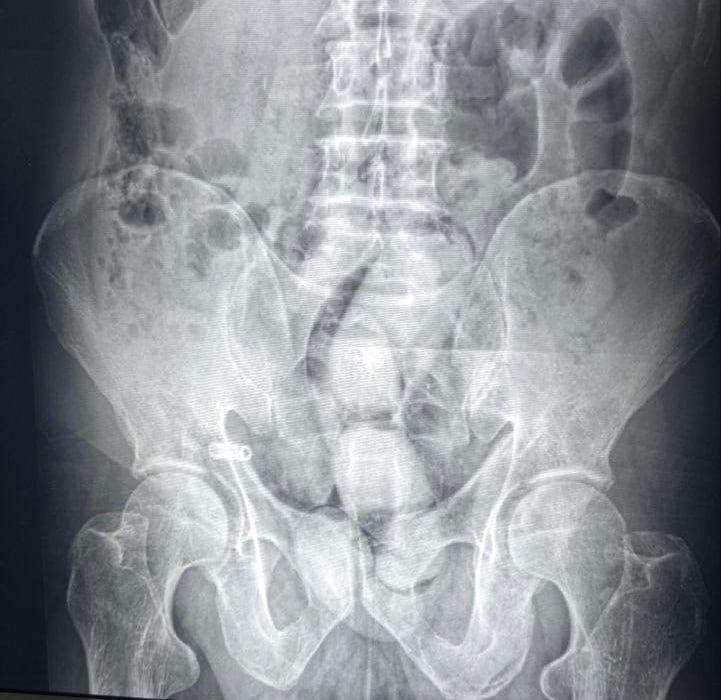

В ходе досмотра были обнаружили три свертка, спрятанные во внутренних полостях тела. После их извлечения было установлено, что в свертках находится 255 граммов опия.

Под наблюдение также попала спутница задержанной женщины. В одной из больниц Самарканда у нее извлекли еще четыре свертка с наркотиком общим весом 541 грамм.